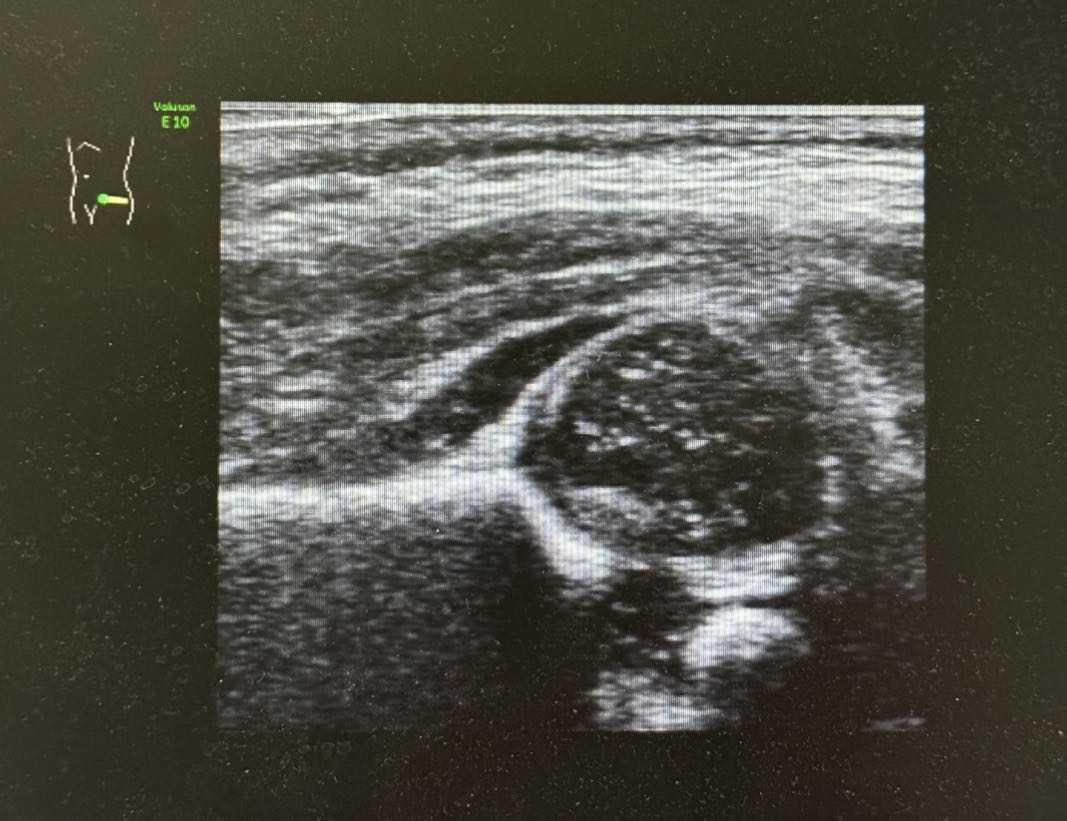

小儿常见病,如肠梗阻、阑尾炎、肠系膜淋巴结炎、肠套叠、Meckel憩室、胆囊炎、泌尿系统结石等可做出快速诊断;同时在幽门肥厚、颅内出血、脑积水、子宫及卵巢的发育监测、髋关节发育不良、感染性病变及肿瘤等方面中有重要诊断价值。